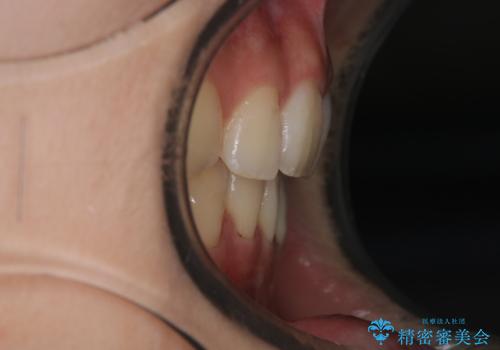

ワイヤーによる抜歯矯正でガタガタの改善

- 前歯のがたがたを主訴に来院されました。

上下の前歯が前方に傾斜しているのもあり、内側に前歯をひっこめるために上下左右の歯を1本ずつ抜歯して矯正することとしました。

ガタガタも改善しましたが、前歯が内側に引っ込むことにより口元もすっきりして、唇が閉じやすくなりました。